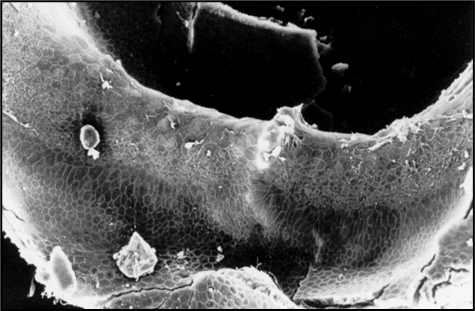

(4/14) Previous #research in our laboratory established that extrusion of #haircells associates with slowly progressing damage as in chronic ototoxicity. In some models, extrusion is by far the main response to chronic ototoxicity

(3/14) Standard experimental approaches had established that #haircells may degenerate by apoptosis. However, loss of #haircells may also proceed through a process of extrusion, in which the cell is ejected from the sensory epithelium

(7/14) Over the last decade, we have published evidence that this detachment of #haircells may occur in rodents and humans, after different ototoxic compounds and after other types of stress (neighbouring #vestibular schwannoma)